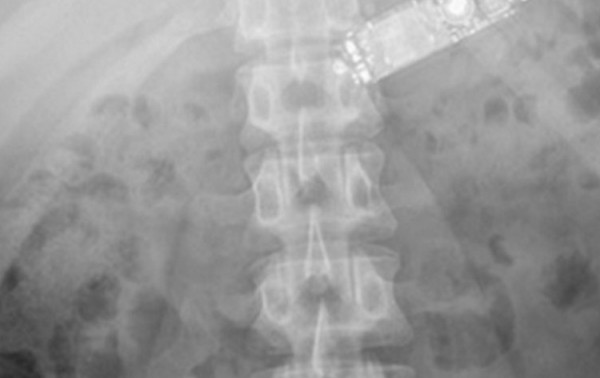

وواجه المسعفون حالة نادرة عندما وجدوا السجين البالغ من العمر 29 عاما في حالة يرثى لها. وأظهر فحص الأشعة السينية أن الهاتف موجود في داخل بطن السجين.

وأظهرت الأشعة السينية ان الهاتف المحمول الذي ابتلعه السجين والبالغ من العمر 29 عاما سليم ولم يتأثر بالحامض المعدي.